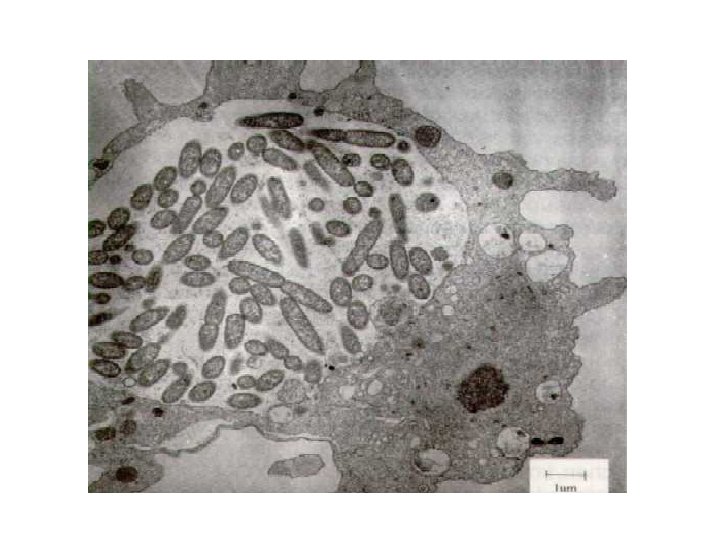

Legionella pneumophila • bactérie aquicole et ubiquiste (eaux de surface, sols humides, eau d’alimentation) • croissance : 20° et 43°C (optimum : 32 -35°C), favorisée par tartre, fer, sédiments, et association avec cyanobactéries, algues ou protozoaires • pathogène opportuniste : pneumonie aiguë • germe témoin de contamination environnementale (eau chaude, bains à remous, brumisateurs, TAR humides)